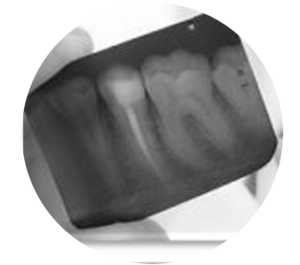

Cuidado Bucal Adultos